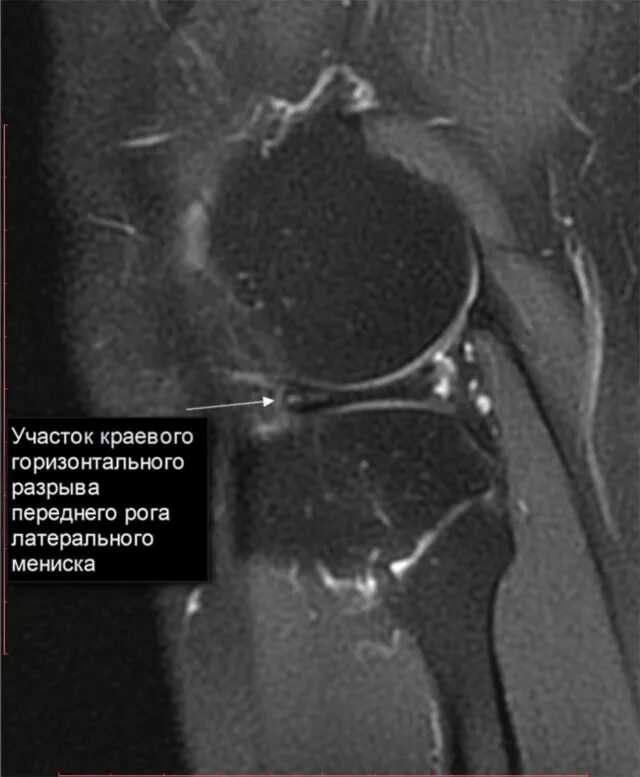

Дегенеративные изменения мениска по stoller